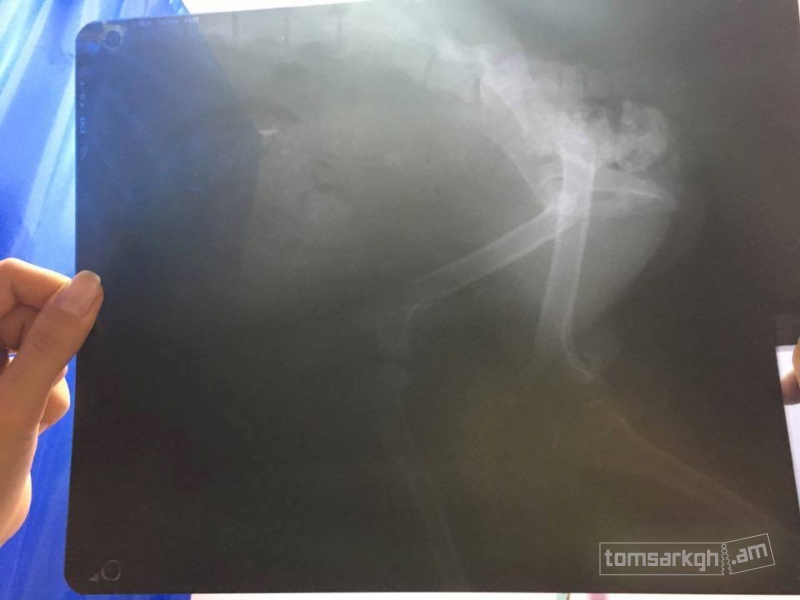

Արևիկին Դինգո կամավորները վերցրին իրենց խնամքի տակ և փորձեցին բուժել, սակայն ապարդյուն։ Մի քանի կիլոգրամ կշռող այս հրաշքն ունի մի շարք խնդիրներ, որոնք ցավոք հայաստանյան պայմաններում բուժել հնարավոր չէ։ Վնասված է Արևիկի ողնաշարը։ Դինգո թիմը չցանկացավ հանձնվել, ուստի որոշում կայացվեց Արևիկին ուղարկել Միացյալ նահանգներ բուժման նպատակով։ Ակնհայտ է, որ մեզ հարկավոր է դրամական օգնություն, ուստի մեր պայքարին միացան նաև մի շարք հայտնի մարդիկ, ովքեր սիրով համաձայնեցին մասնակցել մեր կազմակերպած միջոցառմանը, որի ողջ հասույթը կփոխանցվի մեր շնիկի փրկության գործին։